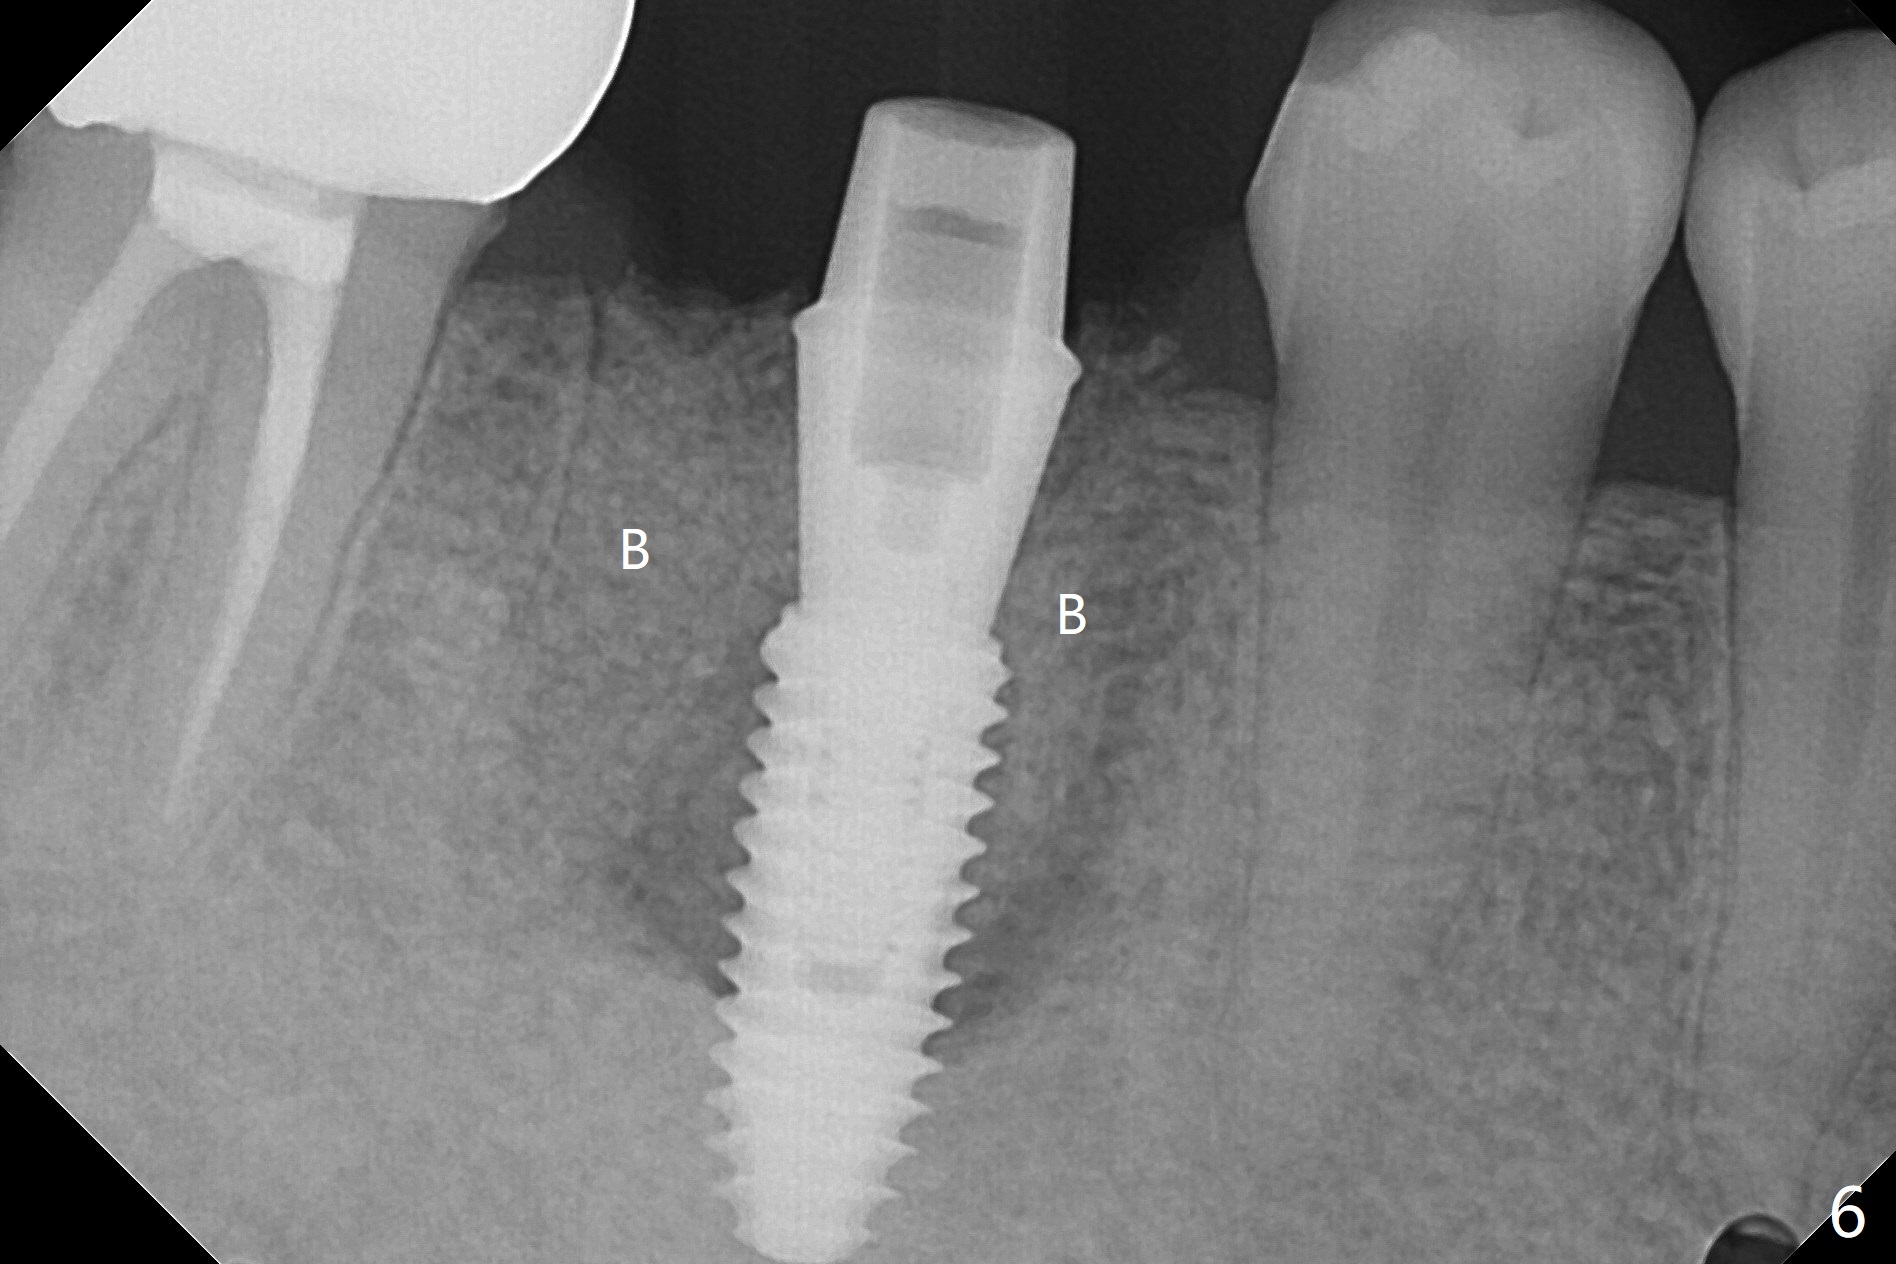

When the tooth #30 is extracted, the gingiva buccal to the septum (S in Fig.1,2 (P: papilla between the mesial and distal roots)) collapses. The latter is fixed with placement of a 4.5x11.5 mm implant (with guide), a 5.2x4(5) mm cemented abutment (Fig.3) and mixture of cortical bone (125μm – 850μm) and cortical/cancellous bone (.5-1 mm) with PRF (sticky bone, B in Fig.4-6). After placement of 2 pieces of PRF membrane over the bone graft, a temporary crown is fabricated to cover the buccal defect (Fig.7 T). Approximately 7.5 mm of the buccal threads are covered by the thick layer of bone graft (Fig.8 B). It is amazing to expect that the bone graft will turn into the buccal plate. It would be better if a narrower implant (4 instead of 4.5 mm) were placed more lingually or there were < 4 mm implant thread exposure (Fig.9). The gingiva reacts to the provisional nicely 7 days postop (Fig.10). The provisional will be removed for modification in 1 month. The patient complains of bad smell from the provisional 2 weeks postop. The provisional is removed. The distal socket (Fig.11 D) is healing, whereas the buccal bone graft (Fig.12 B) seems not have been vascularized. Pedicled flaps (I) should be transferred to cover the buccal bone graft. The margin of the provisional is polished, becomes short, and covered by periodontal dressing, which dislodges 2 days later. One week later, granulation tissue is forming apically with use of oral antibiotic and water jet (Fig.13 *). The bad smell reduces. The superficial loose bone graft changes colar and becomes detached 1 month 10 days postop. The temporary crown with the shortened buccal shelf is reseated for self cleansing or reapplication of PRF if needed (Fig.14).